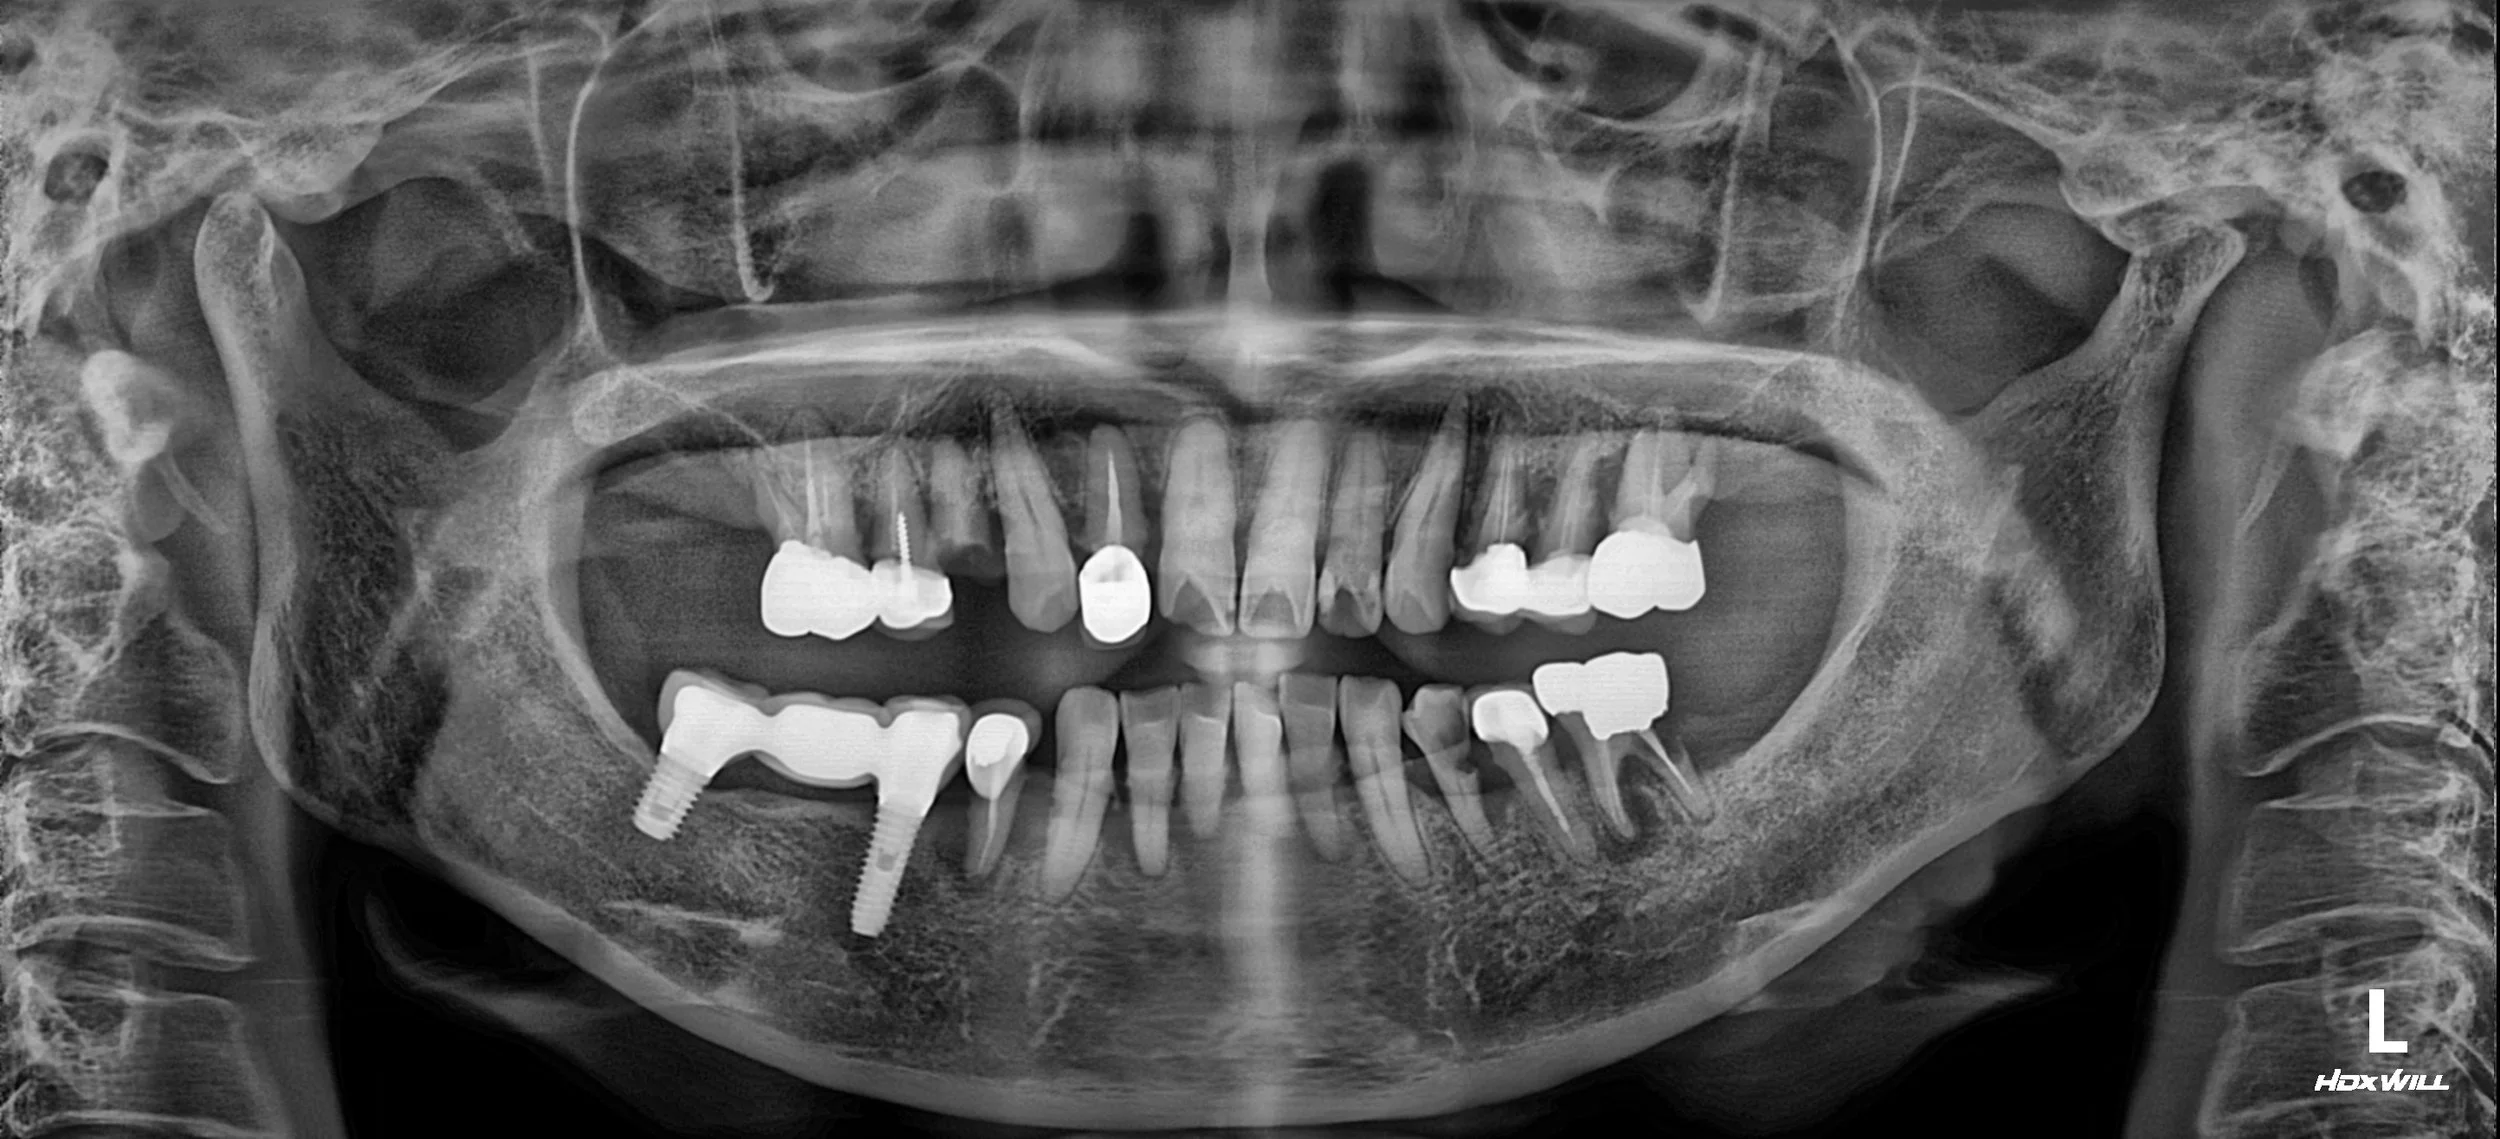

OPG - BEFORE

A female patient in her 60s presented with a severely compromised dentition and significant functional distress. Despite having existing implants, a combination of incorrect occlusal design and poor maintenance had led to:

• Gingival and Occlusal Breakdown: The supporting tissues were inflamed, and the overall bite relationship had collapsed.

• Severe Alveolar Bone Resorption: Long-standing disease around poorly-maintained natural teeth had resulted in extreme vertical and horizontal bone loss.

• Functional Failure: The patient suffered from an inability to chew effectively and was dissatisfied with her aging facial appearance caused by the loss of vertical dimension.